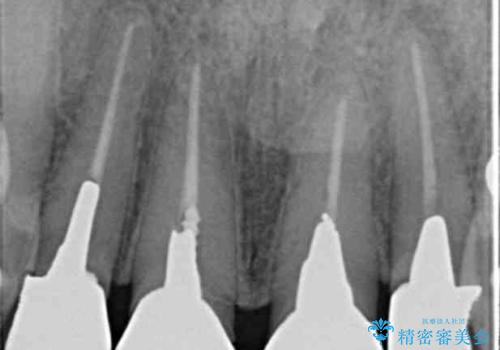

- 「黒ずみの前立つ前歯をやりかえ、きれいにしたい。」と希望され来院されました。

金属色の目立つ前装冠を除去し、発生していた小さな虫歯を丁寧に全て除去しジルコニアセラミッククラウンで審美的な前歯となるような治療を計画します。